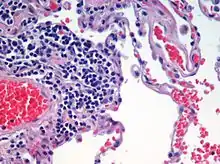

La coloration de tissu biologique est souvent nécessaire pour la mise en évidence et l'identification de cellules ou de la structure tissulaire. Certaines colorations sont compatibles avec la vie cellulaire, d'autres nécessitent la fixation des tissus, et parfois la création de coupes histologiques.

Colorations topographiques

Un colorant consiste souvent en une solution aqueuse contenant un composé portant des groupements chimiques chargés électriquement (fonctions anioniques ou cationiques) et qui peut colorer une ou plusieurs substances de manière stable.

Constitué d'un groupement chromophore (couleur) et d'un groupement auxochrome (groupement ionisé): fixation permanente sur des groupements acides ou basiques des constituants cellulaires (à un pH donné).

- non spécifique d'un type de molécule ;

- donne une vue d'ensemble du tissu : renseigne sur la répartition, l'architecture et la structure des cellules ;

- résulte de l'action conjuguée d'un colorant acide (éosine) et d'un colorant basique (hémalun, bleu de méthylène).

Les substances acides (chargées -) de la cellule sont colorées par un colorant basique (chargé +), les substances basiques (chargées +) de la cellule par un colorant acide (chargé -).[pas clair]

Cette coloration colore un type de charge. On peut voir la morphologie de la cellule (forme), la position du noyau et sa forme. Ainsi, on peut déterminer le nombre de types cellulaires dans le tissu et la structure de ce tissu (cellules collées ou non).